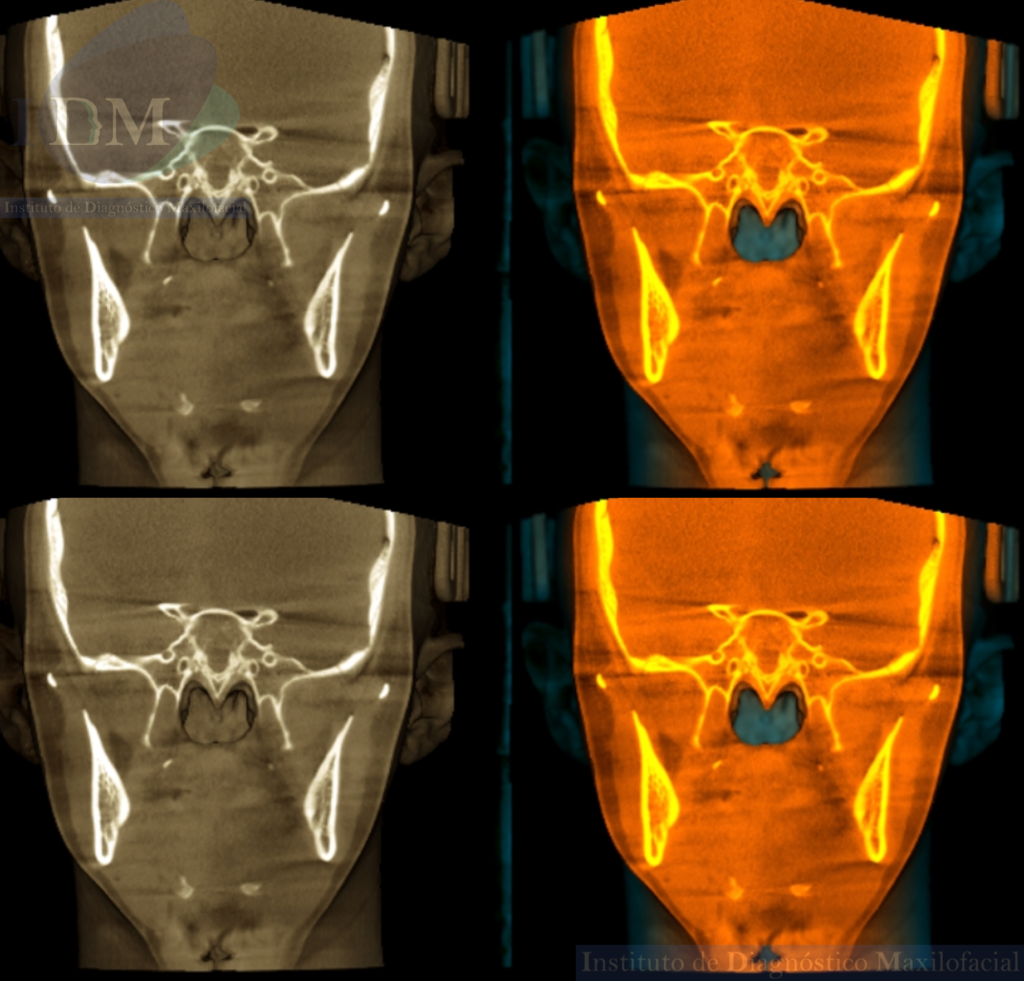

Así mismo en la tomografía volumétrica de haz cónico se evidencia un leve engrosamiento de la mucosa antral de senos paranasales. Siendo lo mas relevante la ausencia de seno esfenoidal en base de cráneo.

RECONSTRUCCIÓN 3D